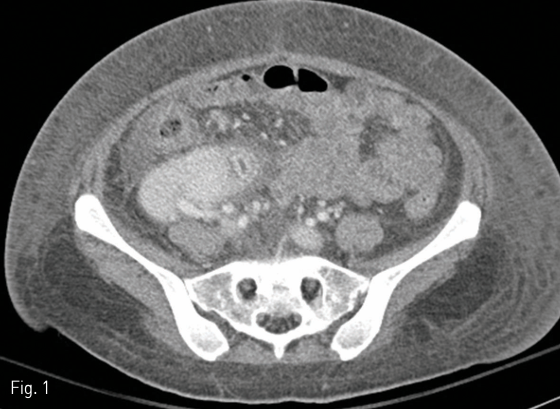

7개월 전 routine follow up으로 시행한 CT 상 우하 복부에 있는 췌장이식 편은 약간 swelling되어 있으나 조영증강은 유지되어 있다(Fig. 1)

On routine follow up CT performed 6 months before the onset of symptoms showed enhancement of transplanted pancreas graft.